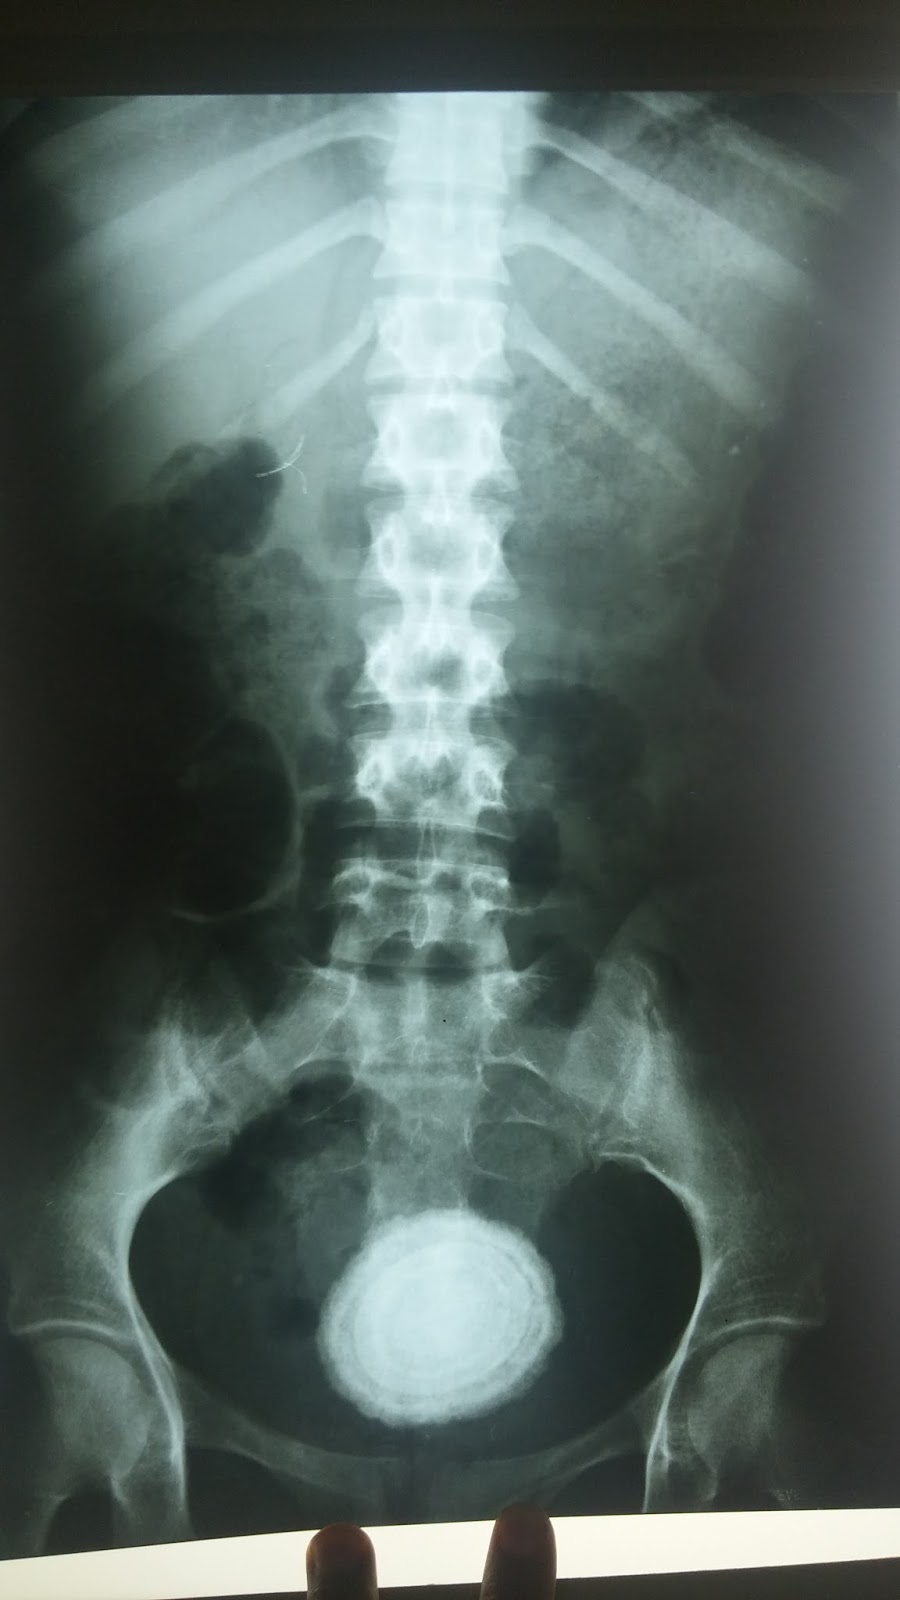

From www.researchgate.net

Xray of urinary bladder taken on 14 May 2007 shows several vesical Crushing Of Stone In The Bladder Is it possible my bladder stones could pass without treatment? A cystolitholapaxy is a surgical procedure that treats bladder stones, which are hard deposits of minerals that can form inside your bladder. Surgery is usually needed to remove the stones from the bladder. Bladder stones—also known as bladder calculi, vesical calculi, or cystoliths—are hardened. They usually form when some urine.. Crushing Of Stone In The Bladder.